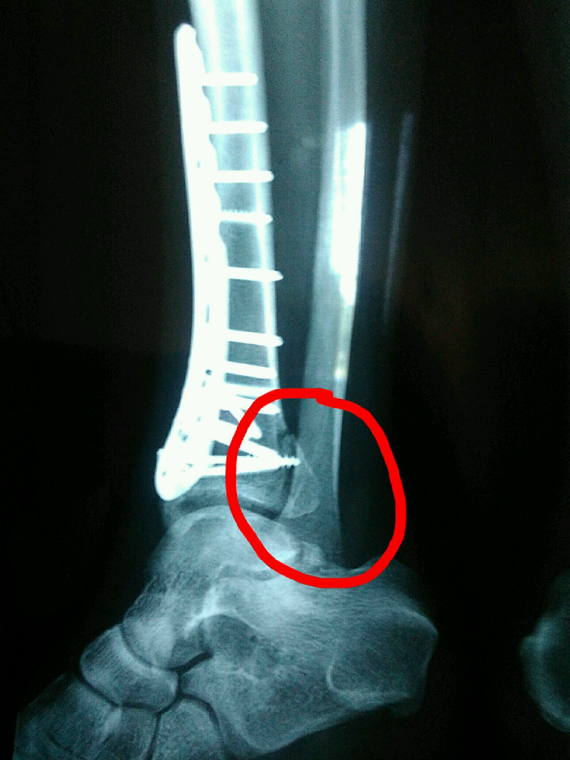

Fracture Du Péroné Sans Plâtre. Fracture de la partie inférieure du péroné, sagittale vue Xray Photo Stock Alamy L'avantage du plâtre est qu'il va quand même parfaitement immobiliser la fracture Si la fracture concerne la diaphyse du péroné, le plâtre devra englober également la moitié de la cuisse

Axe De Fracture D'os De Péroné (os De Jambe) Rayon X De Jambe (position 2 Vue De Face Latérale from fr.dreamstime.com

Axe De Fracture D'os De Péroné (os De Jambe) Rayon X De Jambe (position 2 Vue De Face Latérale

Fracture de la partie inférieure du péroné, sagittale vue Xray Photo Stock Alamy. Quels sont les symptômes de la fracture du péroné ? La durée de récupération après une fracture non déplacée peut varier en fonction de plusieurs facteurs, tels que la gravité de la blessure, l'emplacement de la fracture et le traitement reçu